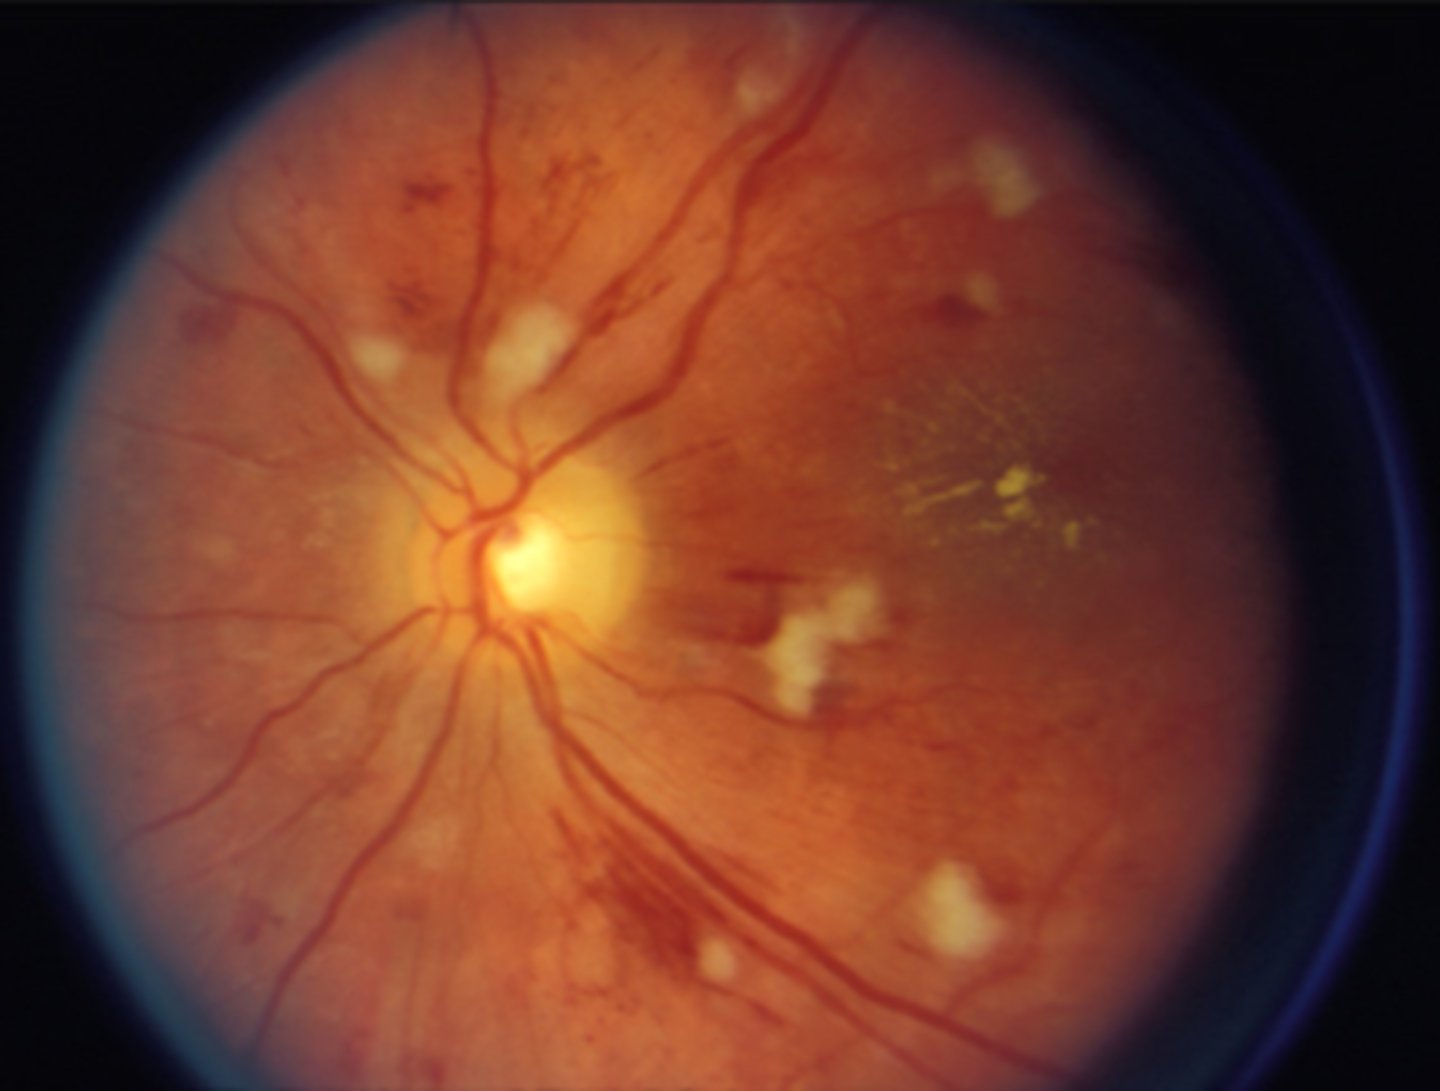

What cause of ascending optic atrophy is shown here?

AAION

grade 4 HTN retinopathy causing disc edema

What finding shown here is a cause of true disc edema?

AAION causing disc edema, flame hemes